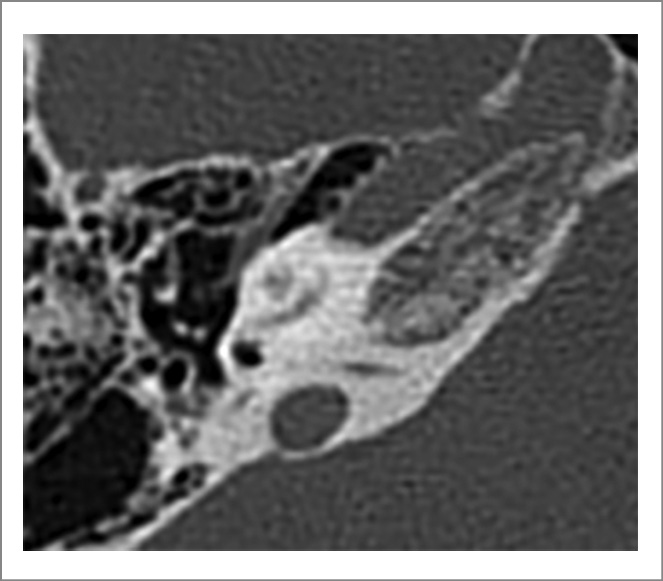

На КТ ВК от 27.03.2022 выявлены КТ-признаки субтотальной оссификации структур лабиринта, СКУ справа частично проходим (рис. 1, 2).

Рис. 1. КТ-картина правой ВК перед операцией.

Рис. 2. КТ-картина левой ВК перед операцией.